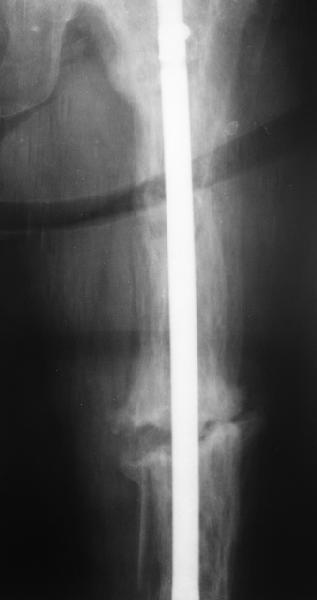

Еще один пример. Пациентка с юга России, прислала рентгенограммы через год. На сегодня прошло 2 г. 8 мес. после операции. Несмотря на не очень убедительный процесс сращения, пациентка ходит. Учитывая остеопороз при Педжете, решили, что динамизировать вообще не нужно.